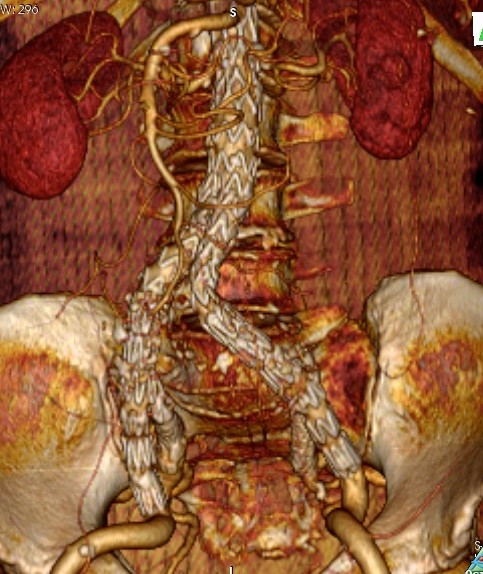

Επιπρόσθετο ανώνυμο φωτογραφικό υλικό

από την αντιμετώπιση ανευρυσμάτων της κοιλιακής αορτής και των λαγονίων αρτηριών

από το προσωπικό μου αρχείο στα Πανεπιστημιακά Νοσοκομεία Λάρισας και Ιωαννίνων

• Περιπτώσεις ανευρυσμάτων κοιλιακής αορτής

• Περιπτώσεις πολύπλοκων ανευρυσμάτων κοιλιακής αορτής